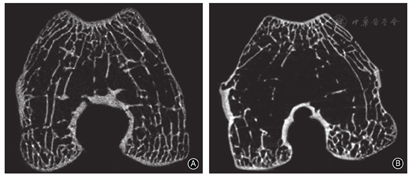

截骨组中1例发生髋关节脱位,而髌骨未发生脱位;3例在屈膝状态下出现完全性的髌骨脱位;16膝在膝关节被动伸直时,髌骨发生脱位。软组织组中15膝在屈膝状态下出现完全性的髌骨脱位,5膝未发生髌骨脱位。截骨组的股骨滑车在滑车入口处伴有局部的突起形成,称为"骨突",而滑车关节面比较光滑,未出现明显的软骨破裂等,而软组织组的股骨滑车未见"骨突"形成,滑车关节面出现软骨破裂、缺损等关节炎表现。与对照组相比,截骨组和软组织组的滑车均变浅和变宽,滑车沟高度和滑车沟角变大,但两组比较没有统计学差异。与对照组相比,截骨组骨小梁发生汇聚,内侧髁和外侧髁的骨小梁厚度增大,内侧髁骨小梁数量减少,而软组织组表现为骨质疏松,内侧髁和外侧髁的骨体积分数、骨小梁厚度、骨小梁数量和骨密度都减少,骨小梁分离度增大。与软组织组相比,截骨组内侧髁和外侧髁的骨体积分数、骨小梁厚度、骨小梁数量和骨密度都较大,骨小梁分离度较小,差异有统计学意义。

截骨组的股骨滑车在滑车入口处伴有局部的突起形成,称为"骨突",入口以远的滑车变宽和变浅,而滑车关节面比较光滑,未出现明显的软骨破裂等。而软组织组的股骨滑车未见"骨突"形成,滑车变宽和变浅,滑车关节面出现软组均裂、缺损等关节炎表现(图4)。

与对照组相比,截骨组的骨小梁厚度在内侧髁和外侧髁分别增加0.03 mm,差异均有统计学意义(t=3.448,P=0.003;t=2.983,P=0.008);骨小梁数量在内侧髁减少了0.41个/mm,差异有统计学意义(t=4.911,P=0.000);而骨体积分数、骨小梁分离度、骨密度以及骨小梁数量(外侧髁)的差异均无统计学意义,显示截骨组滑车骨小梁发生汇聚现象。

与对照组相比,软组织组骨体积分数在内侧髁和外侧髁分别减小7.39%和6.17%,差异均有统计学意义(t=-5.117,P=0.000;t=-5.213,P=0.001);骨小梁厚度均减小0.04 mm,差异均有统计学意义(t=-9.207,P=0.000;t=-5.205,P=0.000);骨小梁数量分别减少0.51个/mm和0.27个/mm,差异均有统计学意义(t=-6.233,P=0.000;t=-2.741,P=0.011);骨小梁分离度分别增大0.50 mm和0.54 mm,差异均有统计学意义(t=9.399,P=0.000;t=9.461,P=0.000);骨密度分别减低0.23和0.19,差异均有统计学意义(t=-20.265,P=0.000;t=-15.199,P=0.000)。这说明软组织组滑车骨小梁发生明显的疏松现象。

而与截骨组相比,软组织组股骨内侧髁和外侧髁的骨体积分数分别减小6.13%和4.18%,差异均有统计学意义(t=4.930,P=0.000;t=2.837,P=0.000);骨小梁厚度分别减小0.05 mm和0.02 mm,差异均有统计学意义(t=3.333,P=0.002;t=2.611,P=0.013);骨小梁数量分别减小0.12个/mm和0.16个/mm,差异均有统计学意义(t=1.304,P=0.000;t=2.052,P=0.041);骨小梁分离度均增大0.43 mm,差异均有统计学意义(t=-9.295,P=0.000;t=-7.686,P=0.000);骨密度分别减低0.15和0.12,差异均有统计学意义(t=3.879,P=0.000;t=2.248,P=0.031)。这说明软组织组滑车骨小梁更加疏松(图6)。

在截骨组中,增大股骨的前倾角可以导致在股骨滑车近端伴有局部骨突形成,内外侧髁局部骨小梁厚度增加,内侧髁骨小梁数量减少。滑车局部的变化是股骨前倾角增加后髌股关节之间压力改变的结果。

股骨前倾角增大后,滑车局部的骨小梁也发生相应变化,表现为内外侧髁局部骨小梁厚度增加,内侧髁骨小梁数量减少。股骨前倾增大后,由于髌股关节匹配性的改变,致髌股关节压力增加,外侧明显大于内侧[22,23],髌股关节之间的接触中心会明显外移[6,7]。这种力的不均衡转移会引起软骨下骨和松质骨的重塑,导致了骨小梁结构相应的变化。

在软组织模型中,由于髌股关节之间压力的下降;内侧软组织松解后,髌骨完全性脱位,髌骨功能障碍引起活动量的减少;以及关节切开术导致局部炎症反应刺激等因素,滑车局部的骨小梁结构发生了类似骨质疏松模式的改变:骨小梁厚度、骨体积分数和骨小梁数量减少,骨小梁距离增加。而由于骨小梁的骨质疏松,易发骨小梁显微骨折,局部血肿,释放炎症因子,引起软骨退变,发生骨关节炎;骨小梁显微骨折致使关节处力线改变,长时间累及造成受力较大的部分软骨发生塌陷,继而再次影响力线,形成恶性循环,最终发生软骨损坏[29,30],因此在软组织模型中,滑车出现了软骨的均裂、缺损等骨关节炎的表现。临床研究业已证实骨质疏松症与退行性膝骨关节炎存在正相关性[30]。